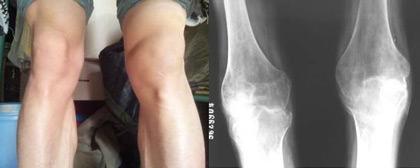

来自焦作市孟州市的王女士来到我院(郑州痛风风湿病医院)进行治疗,王女士的膝盖有些疼痛,疼痛感逐日加重,由最初的红肿演变为双腿行走困难,同时伴有肺炎等并发症。虽然患病期间她一直到处寻医求药,可是治...[详细]